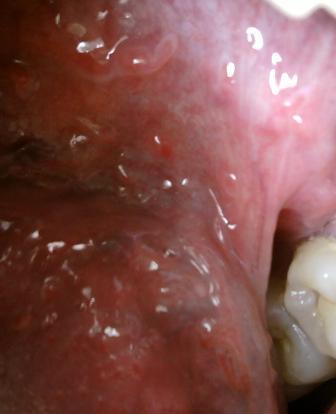

石家庄九州皮肤病医院 > 尖锐湿疣 > > > 请问石家庄哪家医院治疗尖锐湿疣效果好尖锐湿疣是大家比较熟悉的疾病,一般疾病通常发病于年轻的男女,关于尖锐湿疣顽疾,应该早发现早诊治。毕竟早期是治疗疾病的最佳时期。